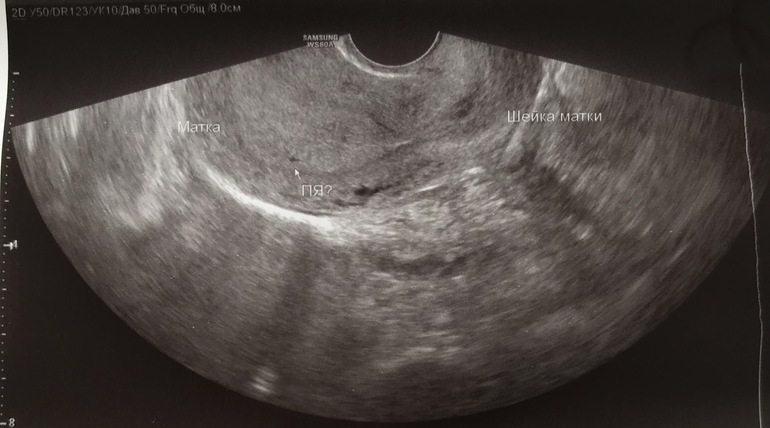

Плодное ли это яйцо?

старшего не помню, было уже 6 недель и, вроде 5 мм было ПЯ, среднюю в 4 недели 2 мм, а сейчас еще ничего не увидели, по мес срок примерно 4 недели тоже, тесты и ХГЧ показывают 2-3 недели и ХГЧ сейчас 422. Говорят, рано...у некоторых и на 10 день задержки не показывает ничего

Алина, ребенок развивается скачками, не по часам. ХГЧ вырос как надо, до 2500 он рос больше чем в 2 раза, после 1000 он в принципе медленнее растет. На хорошем аппарате ПЯ видно от 1500 ХГЧ (вагинально). А вам где делали и как?

у вас и картинка узи какая-то..некачественная что ли. На ПЯ похоже, дай бог на месте и увидите четко. Не переживайте.)